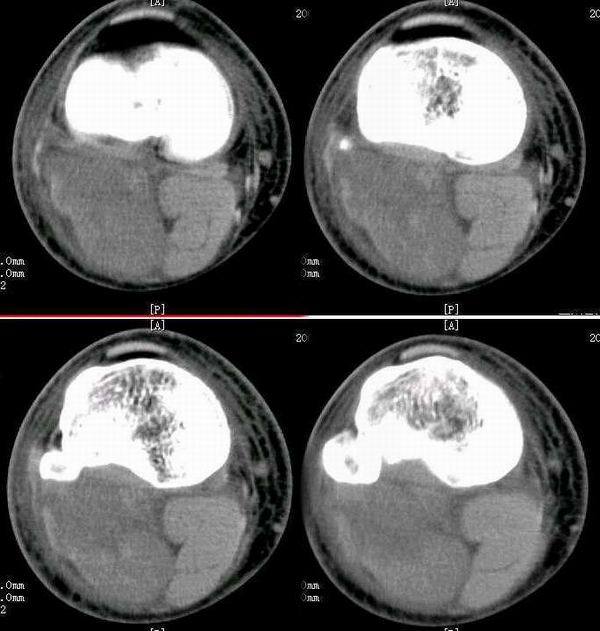

少年全身多发淋巴结肿大,竟是”虫子”惹的祸!|恶性肿瘤|CT检查|淋巴结|-健康界

腹腔及腹膜后多发肿大淋巴结,会是什么呢

腹腔及腹膜后多发肿大淋巴结,会是什么呢

【厦门高尚医学影像病例】PET/CT诊断淋巴瘤的应用价值